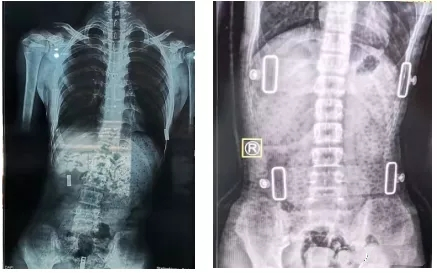

一般我們認為,支具治療3個月后需要進行復查。復查時需要脊柱全長正側位X線片,同時觀察患者支具佩帶區(qū)域皮膚情況。治療過程中如果患者因生長發(fā)育或其他原因造成支具佩戴有不舒服的感覺,需要重新制作支具。支具一般需要持續(xù)佩戴至生長發(fā)育停止,時間隨孩子就診時間以及生長發(fā)育狀況有所不同。

有時戴了支具后脊柱會反方向傾斜。其實,這是因為一般支具治療會采取一種“過度矯正”的方式,以保證脫下支具后身體的反彈更接近于中心線,而不是向原側彎方向加重。